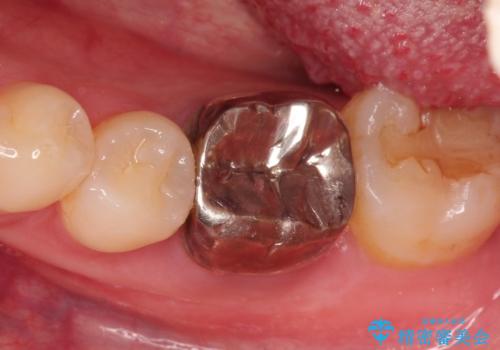

- 下の奥歯の銀歯を白くしたいとのことで来院されました。

痛みなどの症状はなく、前に根管治療を行っている歯になります。

古い銀歯を除去し、審美性の良いセラミッククラウンでの治療を行うこととしました。